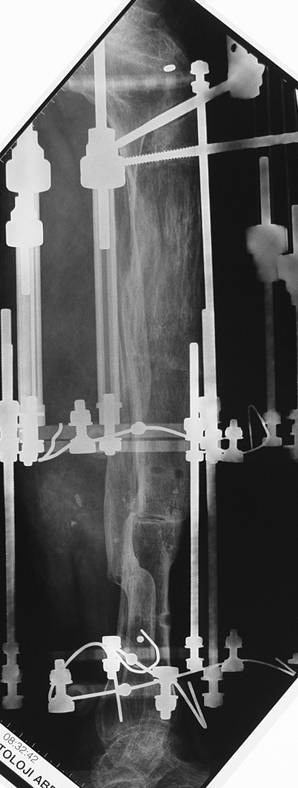

Appropriate radical debridement necessitates excision of all necrotic bone and soft tissues, and frequently causes instability at the involved extremity. The remaining bone and soft tissue defect has to be fixed and reconstructed. The distraction osteogenesis method of Ilizarov is used successfully for achievement of union, correction of the deformity, elimination of limb length inequality and reconstruction of segmental bone defects.

The duration of external fixation (external fixation index) depends on the amount of distraction required, and the extremity is prone to complications during this period. After the distraction phase is completed, the external fixator remains in place during the consolidation phase, which lasts twice as long as the distraction phase; but this period is hardly tolerated. If the external fixator is removed before sufficient consolidation is achieved, fractures, deformity and shortness will be the result. In our department, ‘lenghthening over nail’ method is used in order to decrease the external fixation index and increase patient comfort and activity level. In this method, the intramedullary nail is statically locked after the completion of the distraction phase, and external fixator is removed. The extremity is stabilized by the intramedullary nail during consolidation phase. In this way, complications due to long external fixation index or early removal of the external fixator are avoided.

Case 3